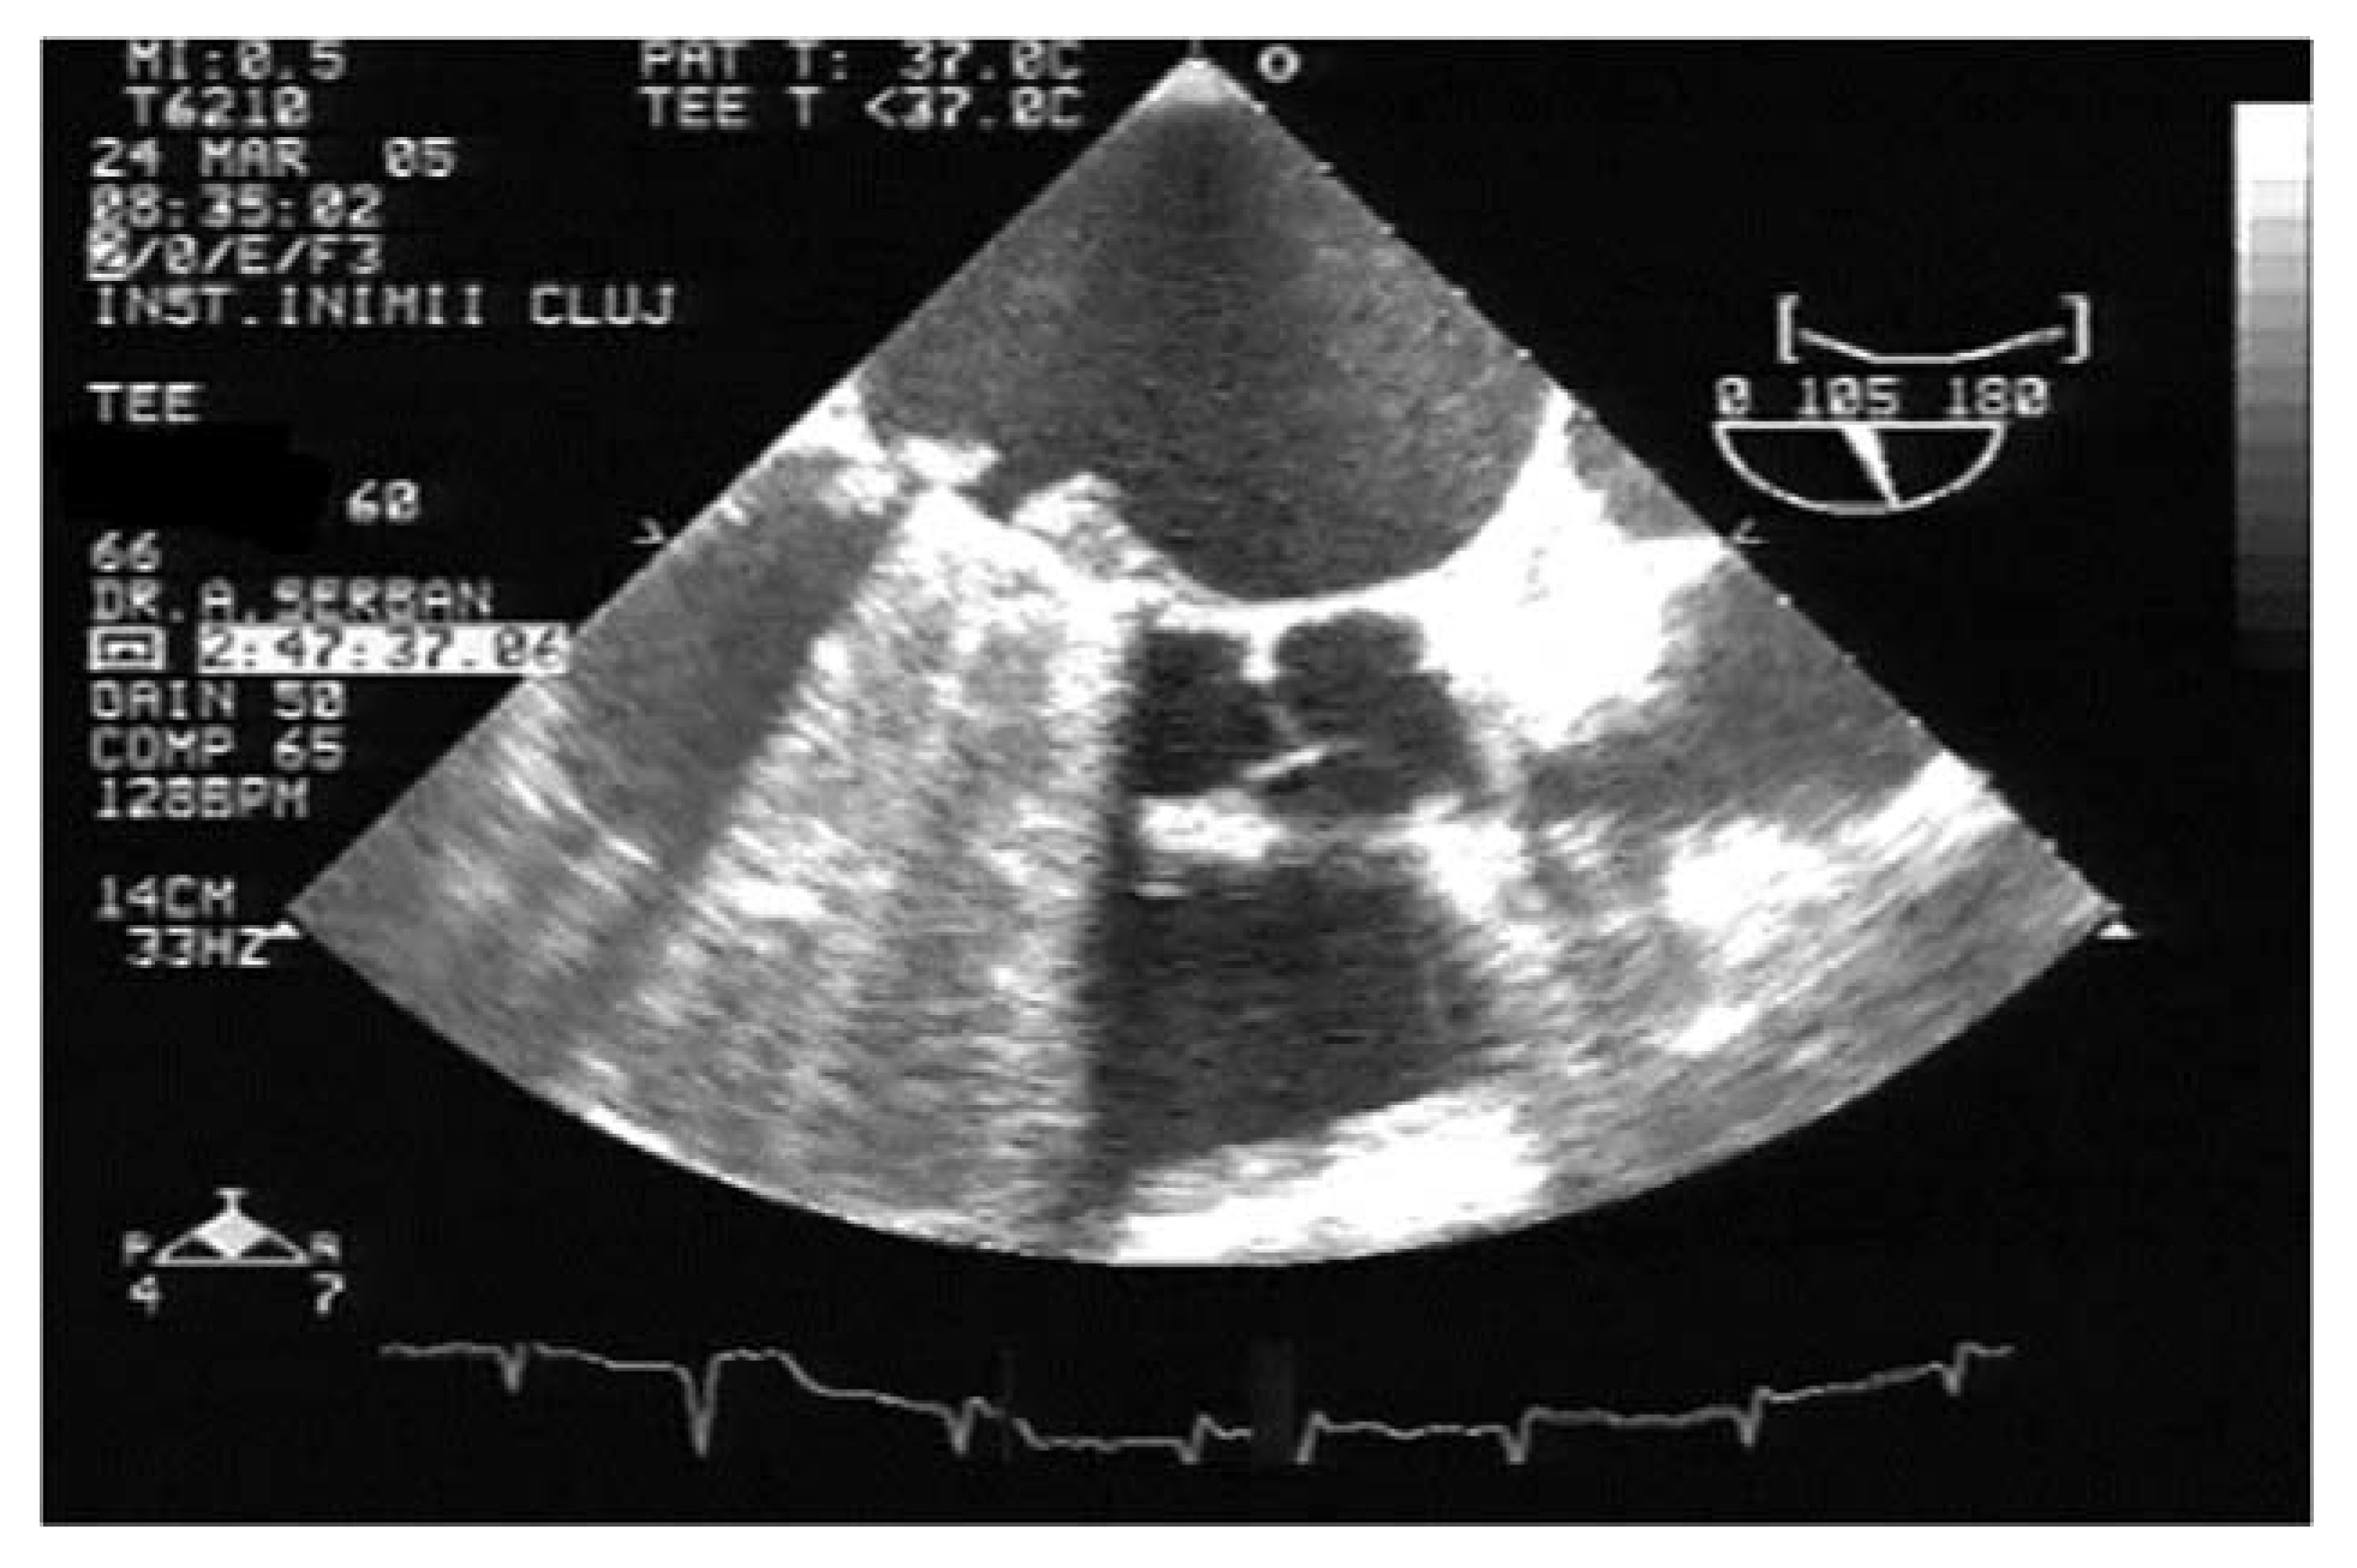

A pannus, in contrast to a thrombus, is a fixed mass with high echogenicity, comparable to that of the prosthetic ring (Figure 3). With the hyperplasia of connective tissue, it progresses from the ring to the prosthesis’ centre. It may also extend to the level of the hinges connecting the discs and the ring. Multidetector computer tomography (MDCT) is the method of choice to distinguish between thrombus and pannus [21,22]. For example, the degree of attenuation for the pannus has been consistently found to begreater than 150–200 Hounsfield Units (HU), while blood or even chronical thrombi have lower HU values [21].

Figure 3.

TEE. Obstructive pannus with high echo density on mechanical mitral valve prosthesis.